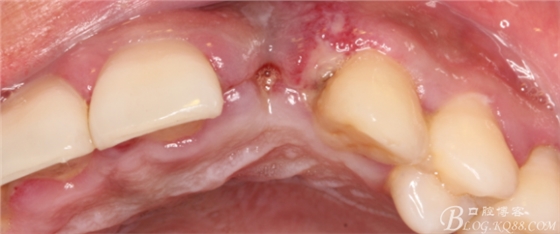

事實(shí)證明,我的做法沒有錯(cuò)誤,一個(gè)月后,軟組織健康愈合。鄰牙軟組織沒有退縮。

再次翻瓣。